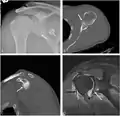

CT scan showing a bony Bankart lesion at the antero-inferior glenoid -

MRI of the shoulder after an anterior dislocation showing a Hill-Sachs lesion and labral Bankart lesion